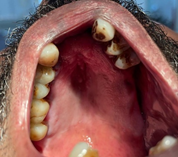

Vital signs were within normal limits. Extra oral examination revealed facial asymmetry (deviation to the left side) with other associated craniofacial abnormalities including a small receding chin indicative of micrognathia, maxillary hypoplasia, depressed frontal bone with prominent eyebrows, exophthalmos, slanting palpebral fissure and a left malar hypoplasia (Figure 2). The mouth opening was normal with a deflection towards the left side. Intraoral examination revealed incomplete cleft palate, and generalized periodontitis with multiple teeth missing (Figure 3).

Figure 3 Intraoral view showing incomplete cleft palate, generalized periodontitis, and multiple missing teeth.

Intellectual function: Most individuals with Nager syndrome have normal cognitive development.3 In this patient, characteristic facial features- such as facial asymmetry, left-sided malar hypoplasia, micrognathia, and maxillary hypoplasia- are consistent with Nager syndrome.9 The incomplete cleft palate further supports this diagnosis, as cleft palate is frequently observed in affected individuals.16 Additionally, the absence of intellectual impairment aligns with typical presentations of Nager syndrome, where normal cognitive function is maintained.17